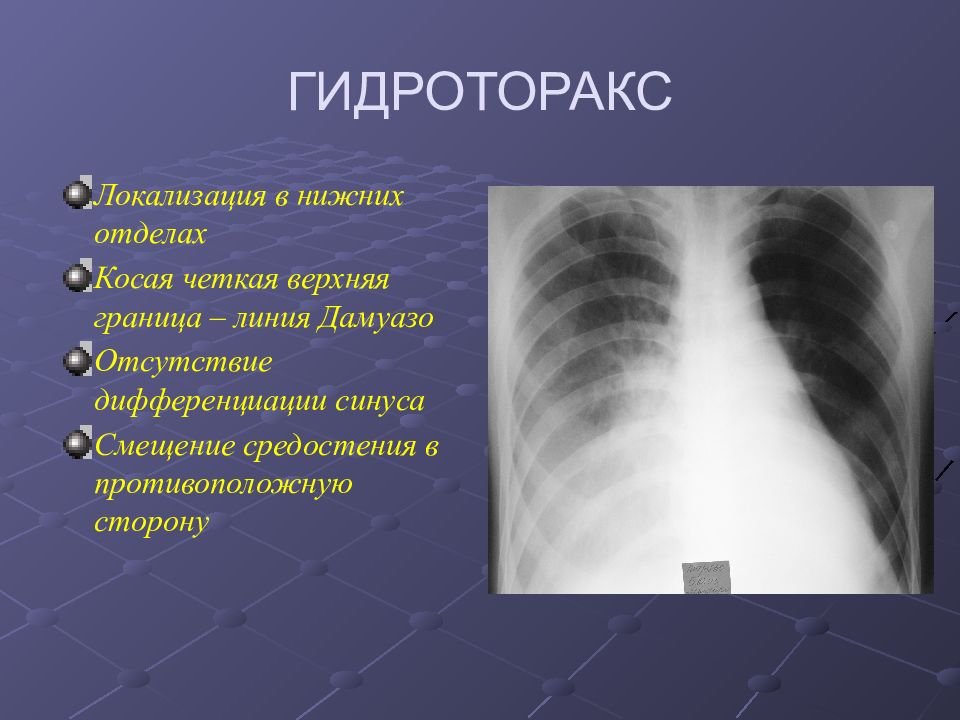

Диагностика плеврального выпота: что нужно знать